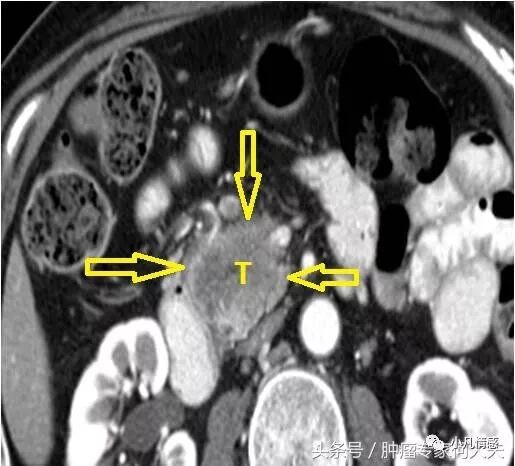

2017年3月再往后的日子,李泉和妻子就奔波于各大医院里,经过全面检查,包括PET-CT,最后确诊为胰腺癌晚期,多发肝转移,多发脾转移,肾上腺转移,腹腔淋巴结转移。41岁的李泉就被确诊为如此重的疾病。显然不可能手术了,胰腺癌号称癌症之王,即便早期,手术后复发和转移概率都非常高,活过2年的都不多,别说这么一个绝对晚期,只能被迫姑息支持治疗,减轻痛苦。后来苦苦支撑了3个多月,李泉的生命画上了句号。在临终阶段,妻子发现平时寡言少语的李泉每天想说的话很多,尽管语声低微,语无伦次,在去世的前3个小时李泉依然清醒,还在吱吱呜呜给妻子交代一些事情。祝福李泉一路走好。内向寡言的他,在生命的最后阶段想开了,可是没机会把话说完。